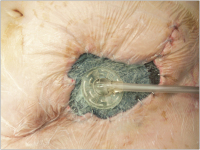

V.A.C.-Therapie

Abbildung 2: Wundkonditionierung durch V.A.C.-Therapie